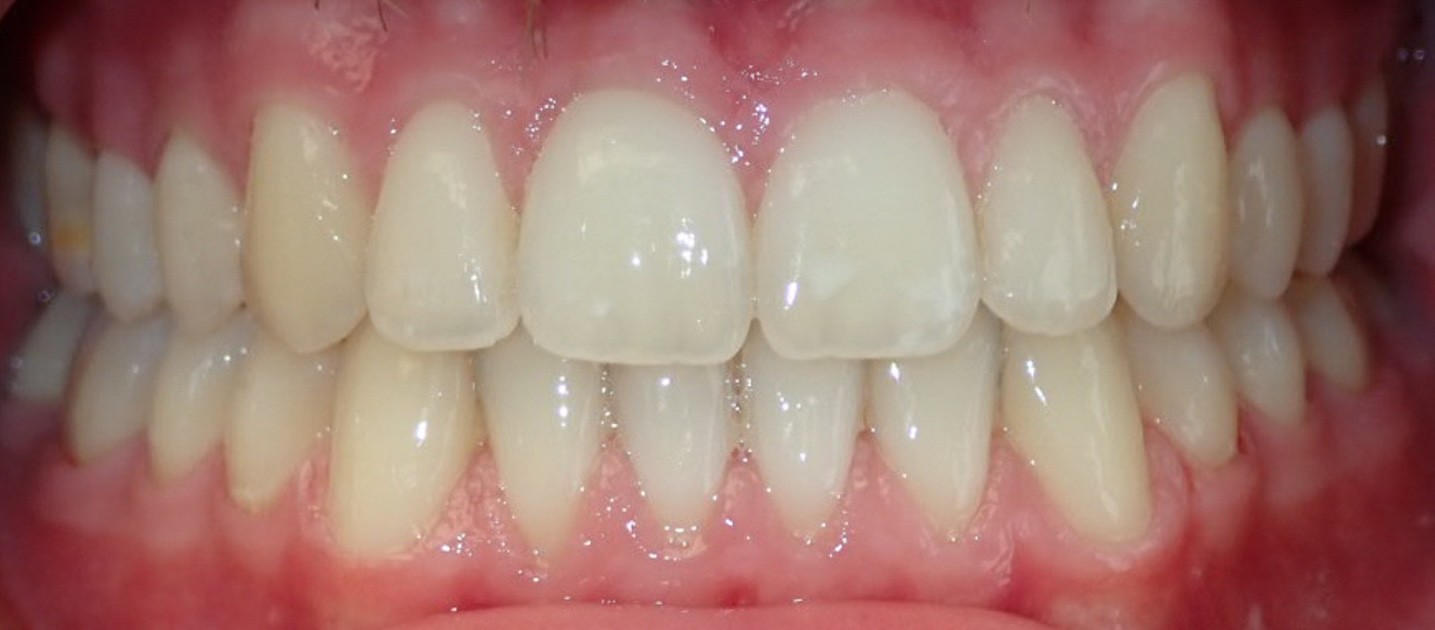

Final results

INTRAORAL